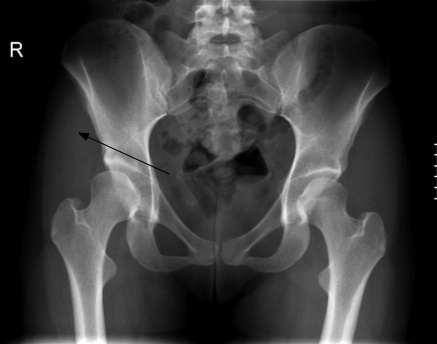

The young adult with a greatly increased range of motion of the hip, particularly if associated with pain in the groin, should be regarded with a high degree of suspicion. X-ray of the pelvis to assess the shape and size of the acetabulum is mandatory.

A 24-year old woman presented six months ago, complaining of chronic thoraco-lumbar pain. There was no mention of hip or groin pain.

Routine examination of the hip revealed greatly increased range of motion of the right hip and, on palpation extreme tenderness of the hip capsule and Pectineus and Adductor magnus muscles. The insertion of the Psoas major in the upper femur was red hot.

X-ray examination of the spine revealed no abnormalities but, in the radiograph of the right hip, the typical shallow acetabulum and partially unroofed head of femur typical of DDH were to be seen. She was not a breech birth, and had no history (I asked her mother to accompany her for the Report of Findings) of hip problems as an infant or in childhood. Certainly there was never mention of HIP DYSPLASIA ORTOLANI GALEAZZI.

My first thoughts before seeing the X-rays were of a Maignes Syndrome, referring pain to the groin. Ultimately I have decided that it's vice versa: The hip is referring pain to the back, mediated via the Psoas major and the Cluneal nerves.